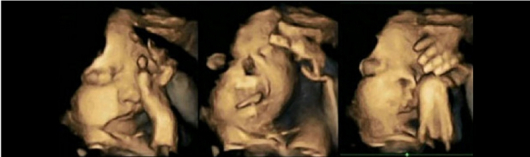

Притеснителните резултати от ултразвука, които специалистите анализирали, доказват, че при ембриони на майки, които пушат движението на ръцете и устата се увеличават драстично. Това пък е сигурен знак за проблем в развитието на централната нервна система на бебето.

Специалистите анализирали резултати от ултразвук на жени, които не пушат и на такива, които употребяват по 14 цигари на ден.

Изследванията показали завишено движение при ембрионите, носени от майки, които пушат. Обикновенобебетата движат устата и ръцете си, но тези движения значително намаляват при наближаване на раждането, тъй като ембрионът започва да се развива и да има все по-голям контрол над моторните си функции.

Учените предполагат, че това се дължи на факта, че никотинът забавя развитието на централната нервна система на детето, която контролира движенията му.